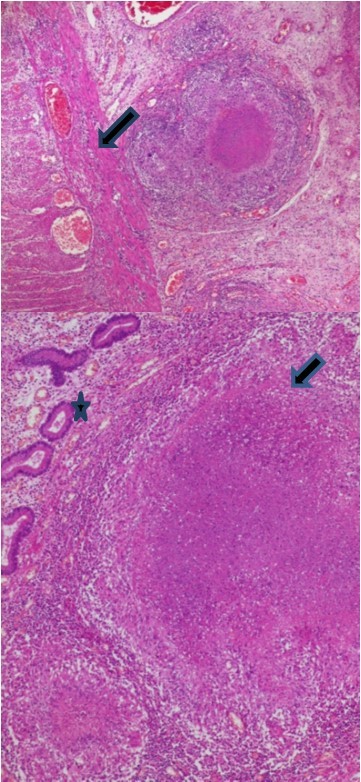

The histopathologic examination of the resected bowel specimen showedcaseating granulomatous inflammation (Figure 2), consistent with intestinal small bowel tuberculosis complicated with peritonitis and perforation (Figure 3).

Figure 2.Epithelioid granuloma and giant cells (Arrow) with caseous necrosis (Star)

Figure 3.Signs of acute peritonitis in the intestinal mucosa